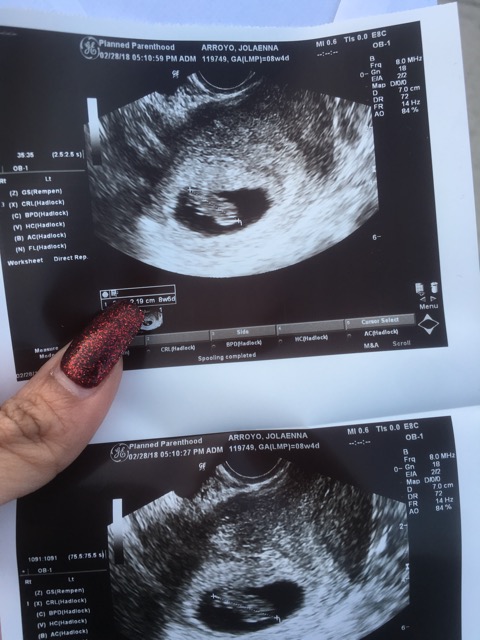

Ramzi theory

I'm curious to see what this is all about what do you ladies think boy or girl ?